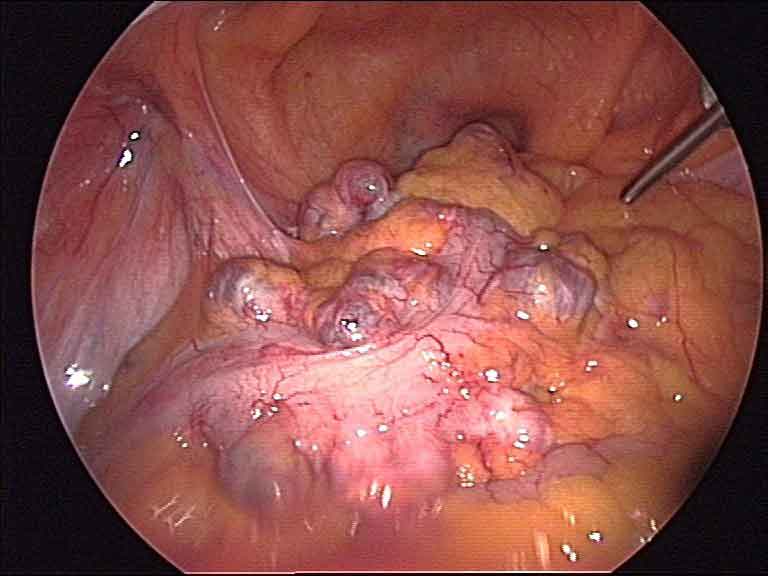

Laparoscopic view inside abdomen during colon cancer surgery

Colon Cancer

Laparoscopic Colon Cancer Surgery

Keyhole removal of the affected section of the colon — including right hemicolectomy, left hemicolectomy, and total colectomy. The magnified camera view allows precise dissection around blood vessels and lymph nodes.